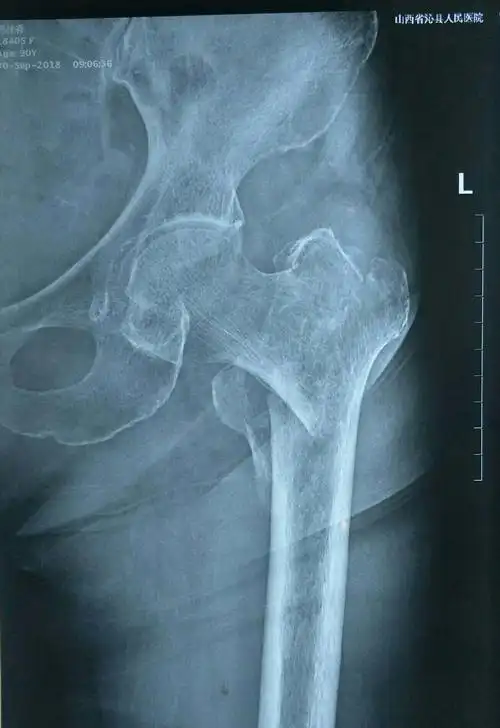

左侧股骨粗隆间骨折(改良evens三型) - 美篇